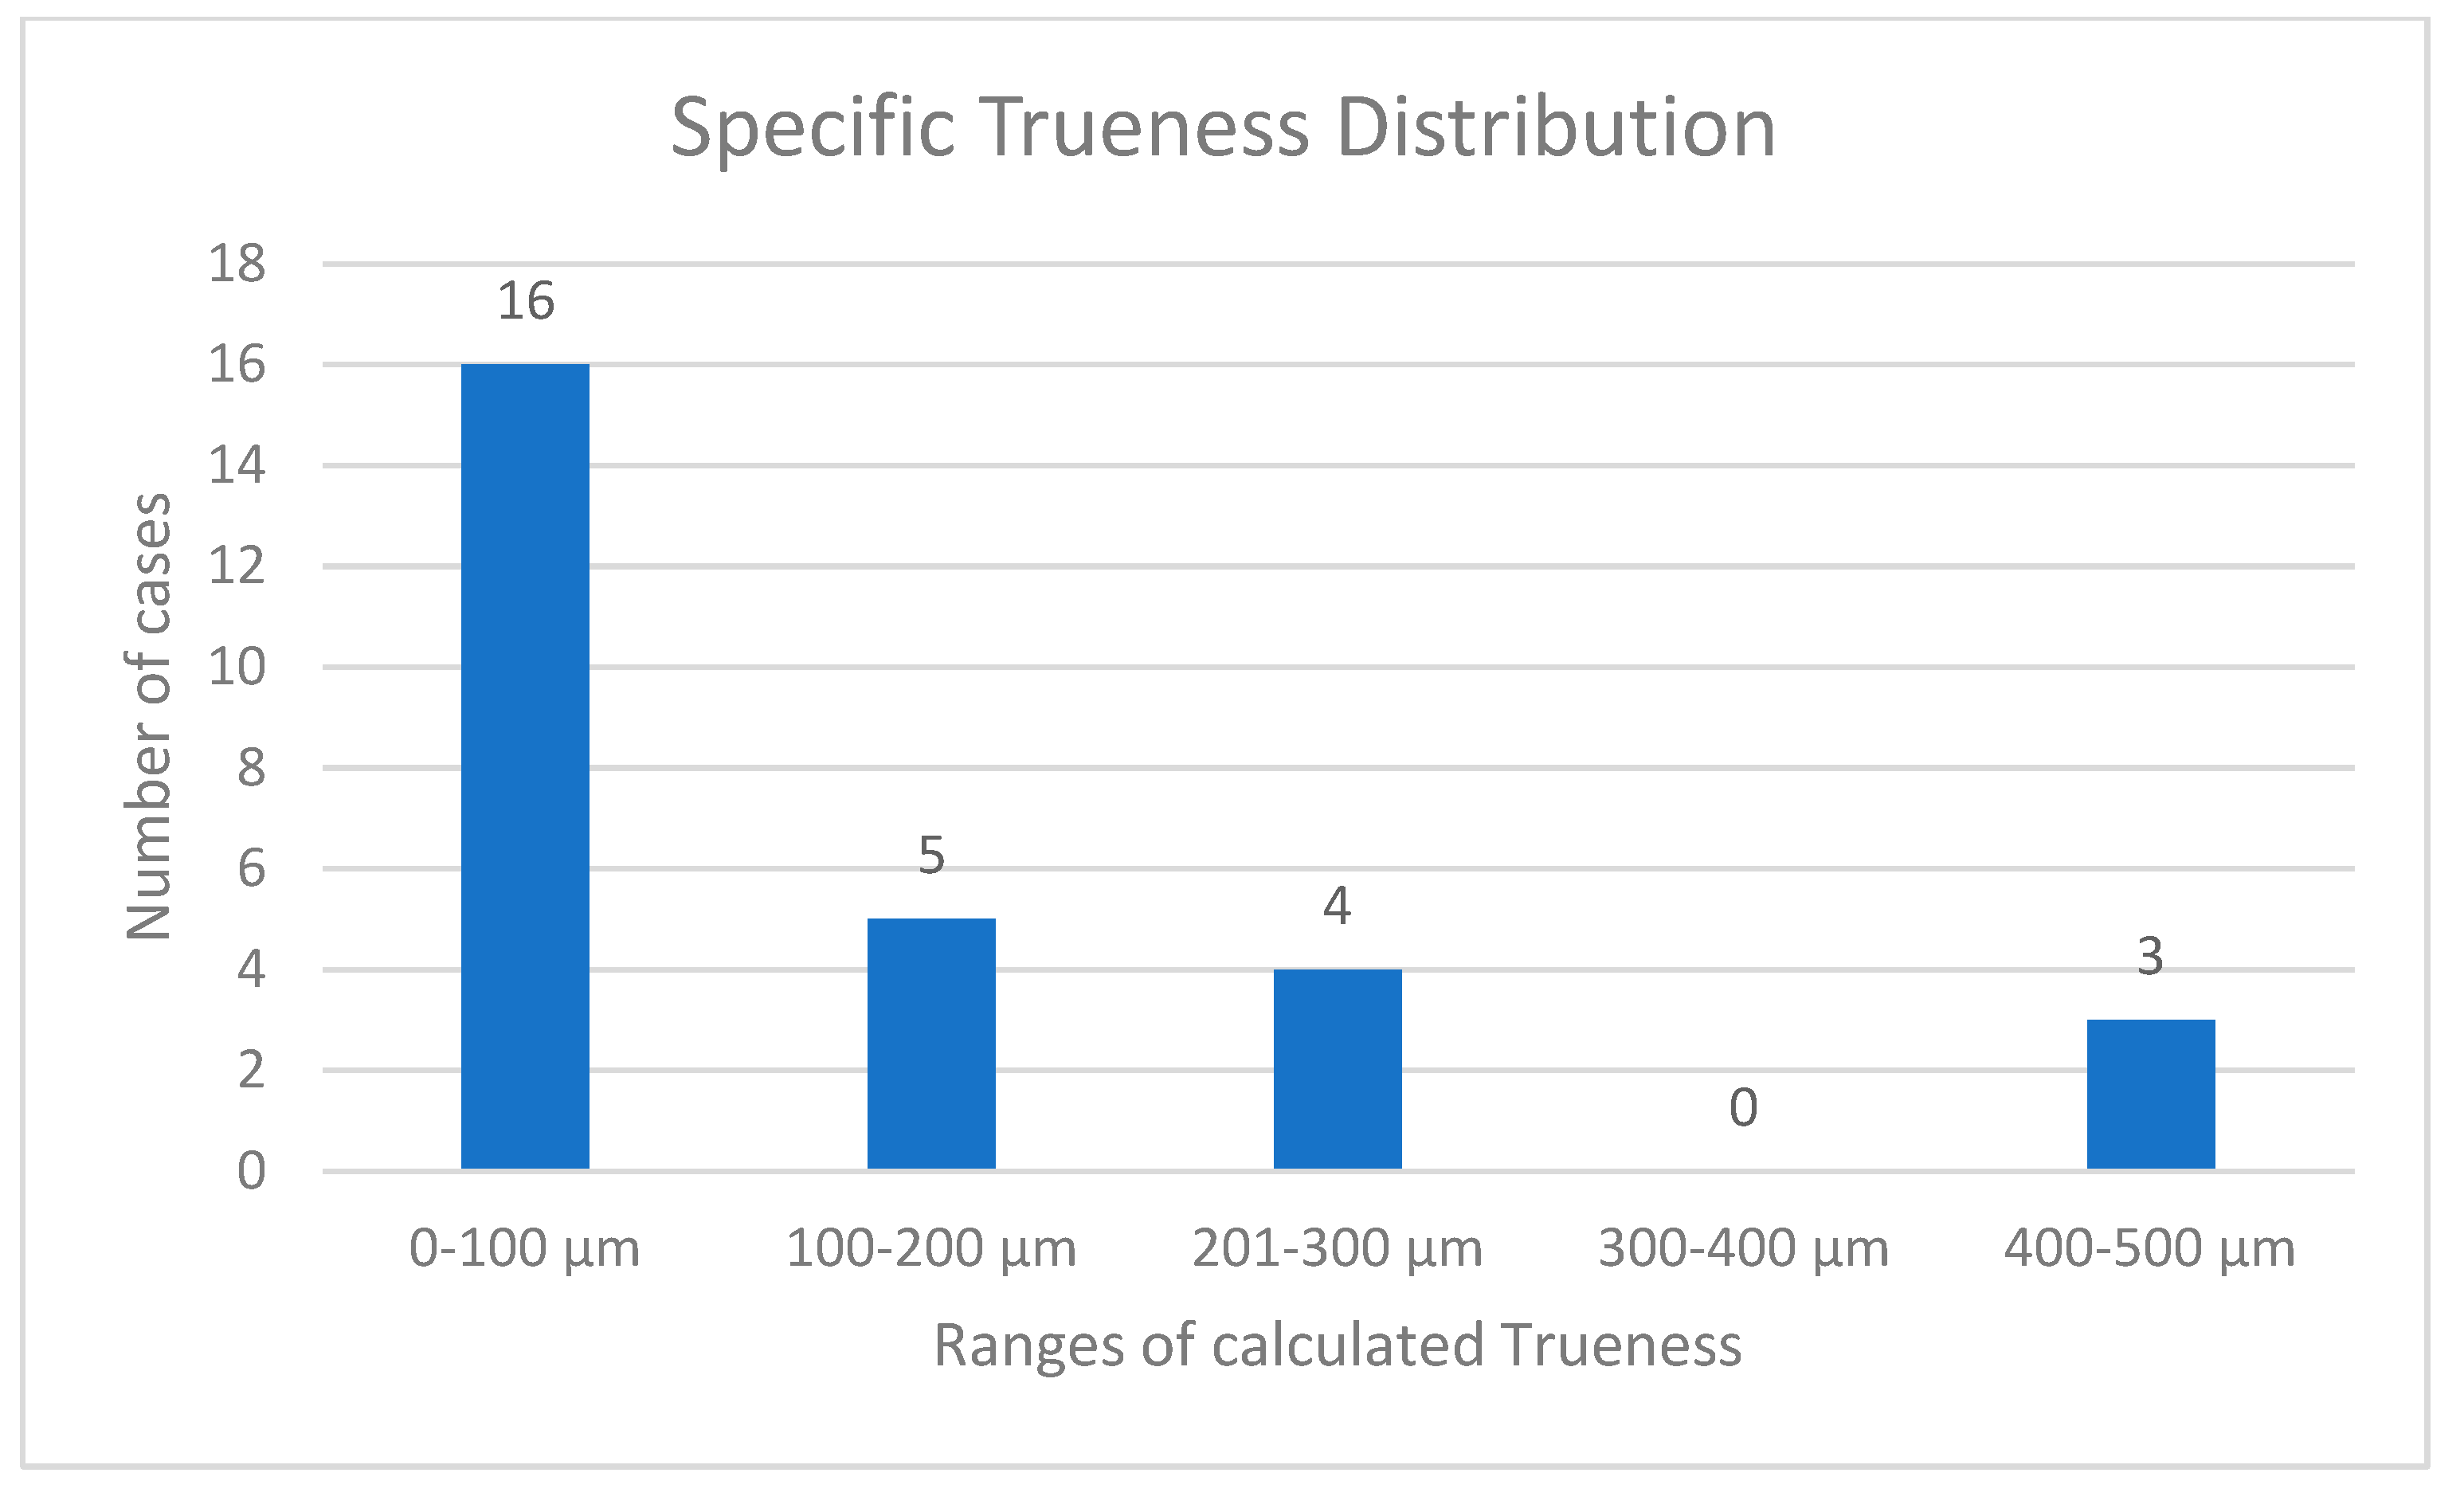

3. Results

- Despite the limitations of this pilot study, the authors suggest that the gypsum check screwed onto implant abutments is an effective method to quickly detect the Trueness and Accuracy values of digital impressions, considering, respectively, cut-off threshold values of 100 µm for Trueness and 98% for Accuracy percentage.

- Considering that the passive fit of the framework plays a central role in prosthetic rehabilitations which involve multiple implants, the authors propose 100 µm as a maximum clinical tolerance misfit value: at values over 100 µm of misfit, the impression could not be considered reliable because it does not allow the passive fit of future prosthetic frameworks.